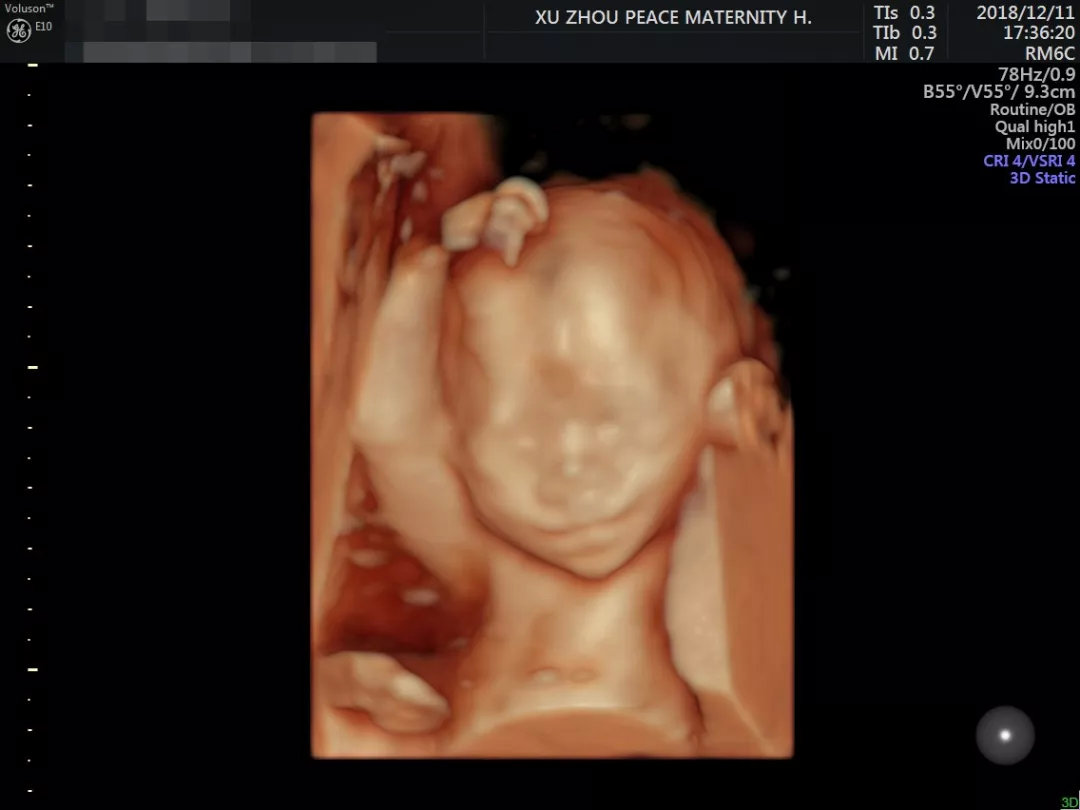

22-26周时,宝妈们就可以去做四维彩超,通过四维彩超看见宝宝的动态影像,甚至看到宝宝的手脚、宝宝的面部大概轮廓以及他们的表情动作。

一些活泼的宝宝也在这里提前向爸爸妈妈们展示了自己的幽默细胞,不信,你看:

闲着没事挠挠头

想知道宝宝在肚子里干什么,最直观的办法就是通过四维彩超。四维彩超不仅能让孕妈看到宝宝的样子,也是孕期检查相当重要的一环,能筛查胎儿各项器官的发育情况,为先天性体表畸形和先天性心脏病的筛查提供科学依据。